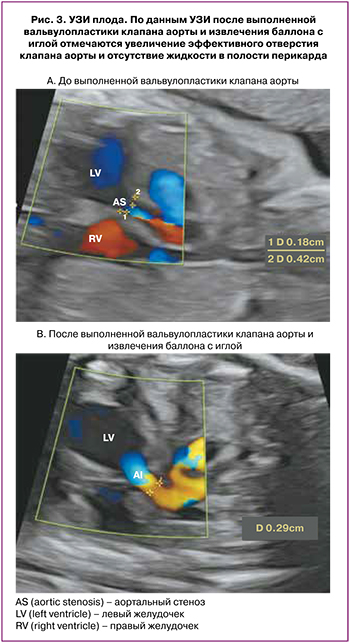

После того как были получены удовлетворяющие результаты операции, комплекс игла/коронарный проводник/баллон был извлечен одномоментно, во избежание повреждения баллона и эмболии его частей, что возможно при раздельном извлечении. После завершения операции с целью оценки функции АК было проведено контрольное УЗИ. Еще одной задачей контрольного УЗИ было исключение одного из возможных осложнений операции: наличия жидкости в полости перикарда.

После проведения процедуры диаметр эффективного отверстия АК составил 2,9 мм. Жидкости в полости перикарда не обнаружено (рис. 3).

По данным УЗИ после выполненной вальвулопластики клапана аорты и извлечения баллона с иглой отмечаются увеличение эффективного отверстия клапана аорты и отсутствие жидкости в полости перикарда.

Через 12 ч после операции было проведено УЗИ сердца плода. Фракция выброса ЛЖ увеличилась до 24%, диаметр эффективного отверстия АК составил 2,9 мм. Максимальный градиент на АК возрос до 21 мм рт. ст., митральная регургитация уменьшилась с тотальной до 2-й степени. Жидкости в полости перикарда обнаружено не было.